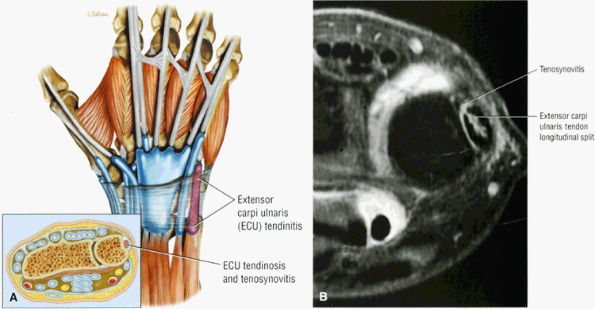

FIGURE 10.15 ● EXTENSOR CARPI ULNARIS The extensor carpi ulnaris tendon extends and adducts the wrist. It is commonly affected in tendinosis and tenosynovitis as it passes through the groove on the distal ulna. Subluxation of the extensor carpi ulnaris can also occur at this location related to disruption or insufficiency of the ligament that covers the tendon in this groove. The extensor carpi ulnaris tendon subsheath is a component of the triangular fibrocartilage complex.

|